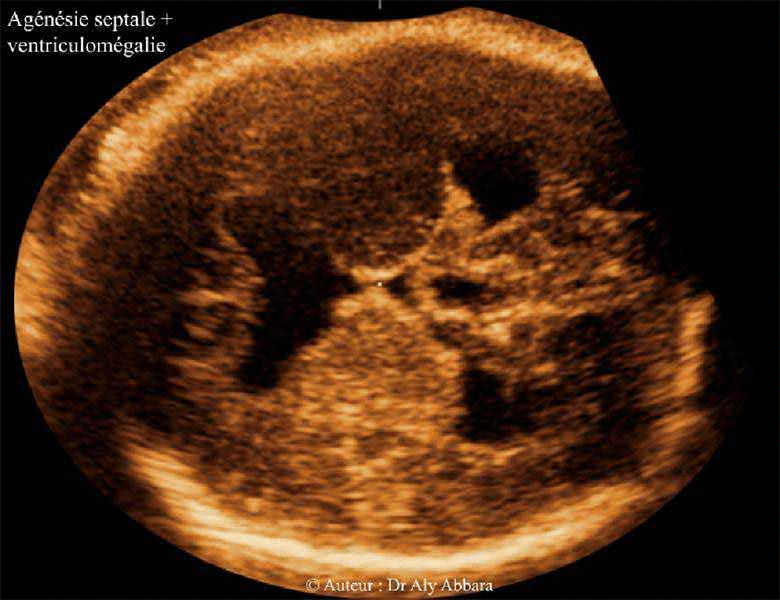

Agénésie septale totale - Foetus de 34 SA - Echographie 1

Agénésie septale caractérisée par l'absence du septum pellucidum et la fusion des cornes antérieures des ventricules latéraux avec ventriculomégalie bilatérale - le corps calleux est présent

Images échographiques et IRM : coupe axiale